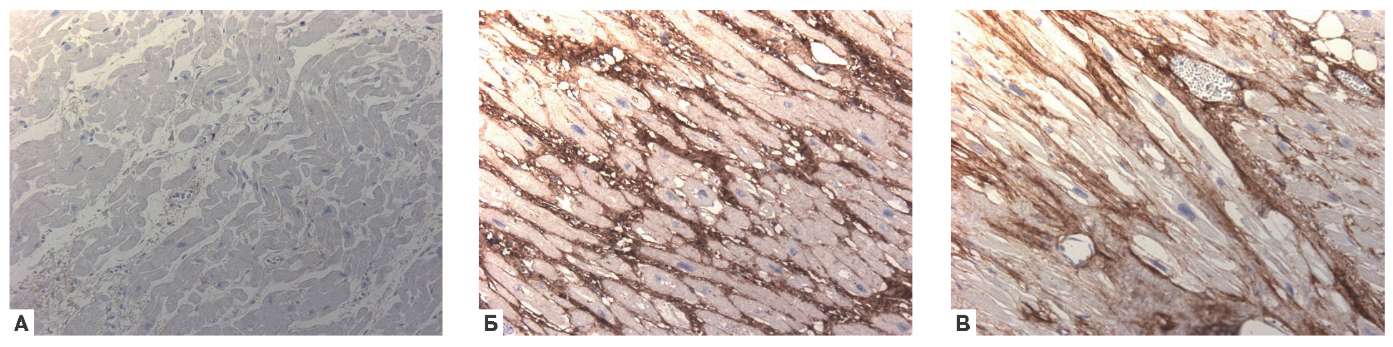

ИГХИ с антителами к коллагенам I и III фрагментов верхней части задней стенки ЛП во всех изучаемых группах ФП и без нее с оценкой экспрессии в баллах (рис. 3, 4) выявило сильную положительную корреляционную связь ФП с коллагеном III (r=0,869, p<0,01) и отсутствие связи с коллагеном I.

Рис. 3. ИГХИ ЛП с антителами к коллагенам. А — отсутствие экспрессии коллагена III в стенке предсердия у пациента без ФП. Б — экспрессия коллагена III (коричневое окрашивание; 4 балла), фиброз — оплетка при длительно персистирующей ФП; В — экспрессия коллагена I (коричневое окрашивание; 3 балла) вокруг мышечных волокон у пациента с пароксизмальной ФП; х200.